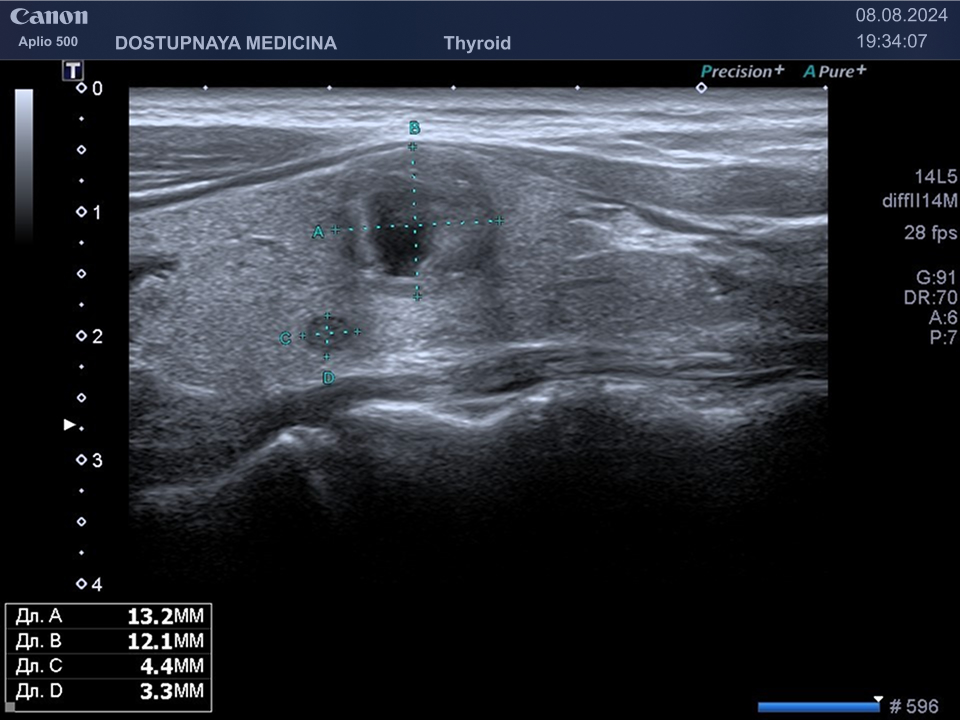

В ультразвуковой диагностике существует классификация образований щитовидной желзы по TIRADS, которая по различным критериям определяет степень онкоопастности того или ионого узла. При оценке учитывается эхоструткура образования ( кистозная, губчатая, солидная или солидно-кистозная), эхогенность ( анэхогенное, гиперэхогенное, гипоэхогенное), пространственная ориентация горизонтальная, вертикальная, неопределённая), контуры образования (ровные, дольчатые, зазубренные с острыми углами), наличие эхогенных включений( макрокальцинаты, микрокальцинаты, периферическая кольцевидная кальцификация). В зависимости от этих критериев выделяют различные категориии объёмных образований в щитовидной железе:

TIRADS 3 – низко подозрительное образование, требующие динамическое наблюдение и тонкоигольной биопсии при размерах узла больше 2.5 см.

TIRADS 4 – умеренно подозрительное образование, требующие динамическое наблюдение и тонкоигольной биопсии при размерах узла больше 1.5 см.

TIRADS 5 – высоко подозрительное образование, требующие динамическое наблюдение и тонкоигольной биопсии при размерах узла больше 1 см.

Большинство узловых образований в щитовидной железе не нуждаются в лечении и требуют лишь наблюдения путём повторного ультразвуковых исследований.

При подозрении на озлокачествление и увеличении узла в размерах требуется тонкоигольная пункционная биопсия с полседующим цитологическим исследованием, полученного материала.